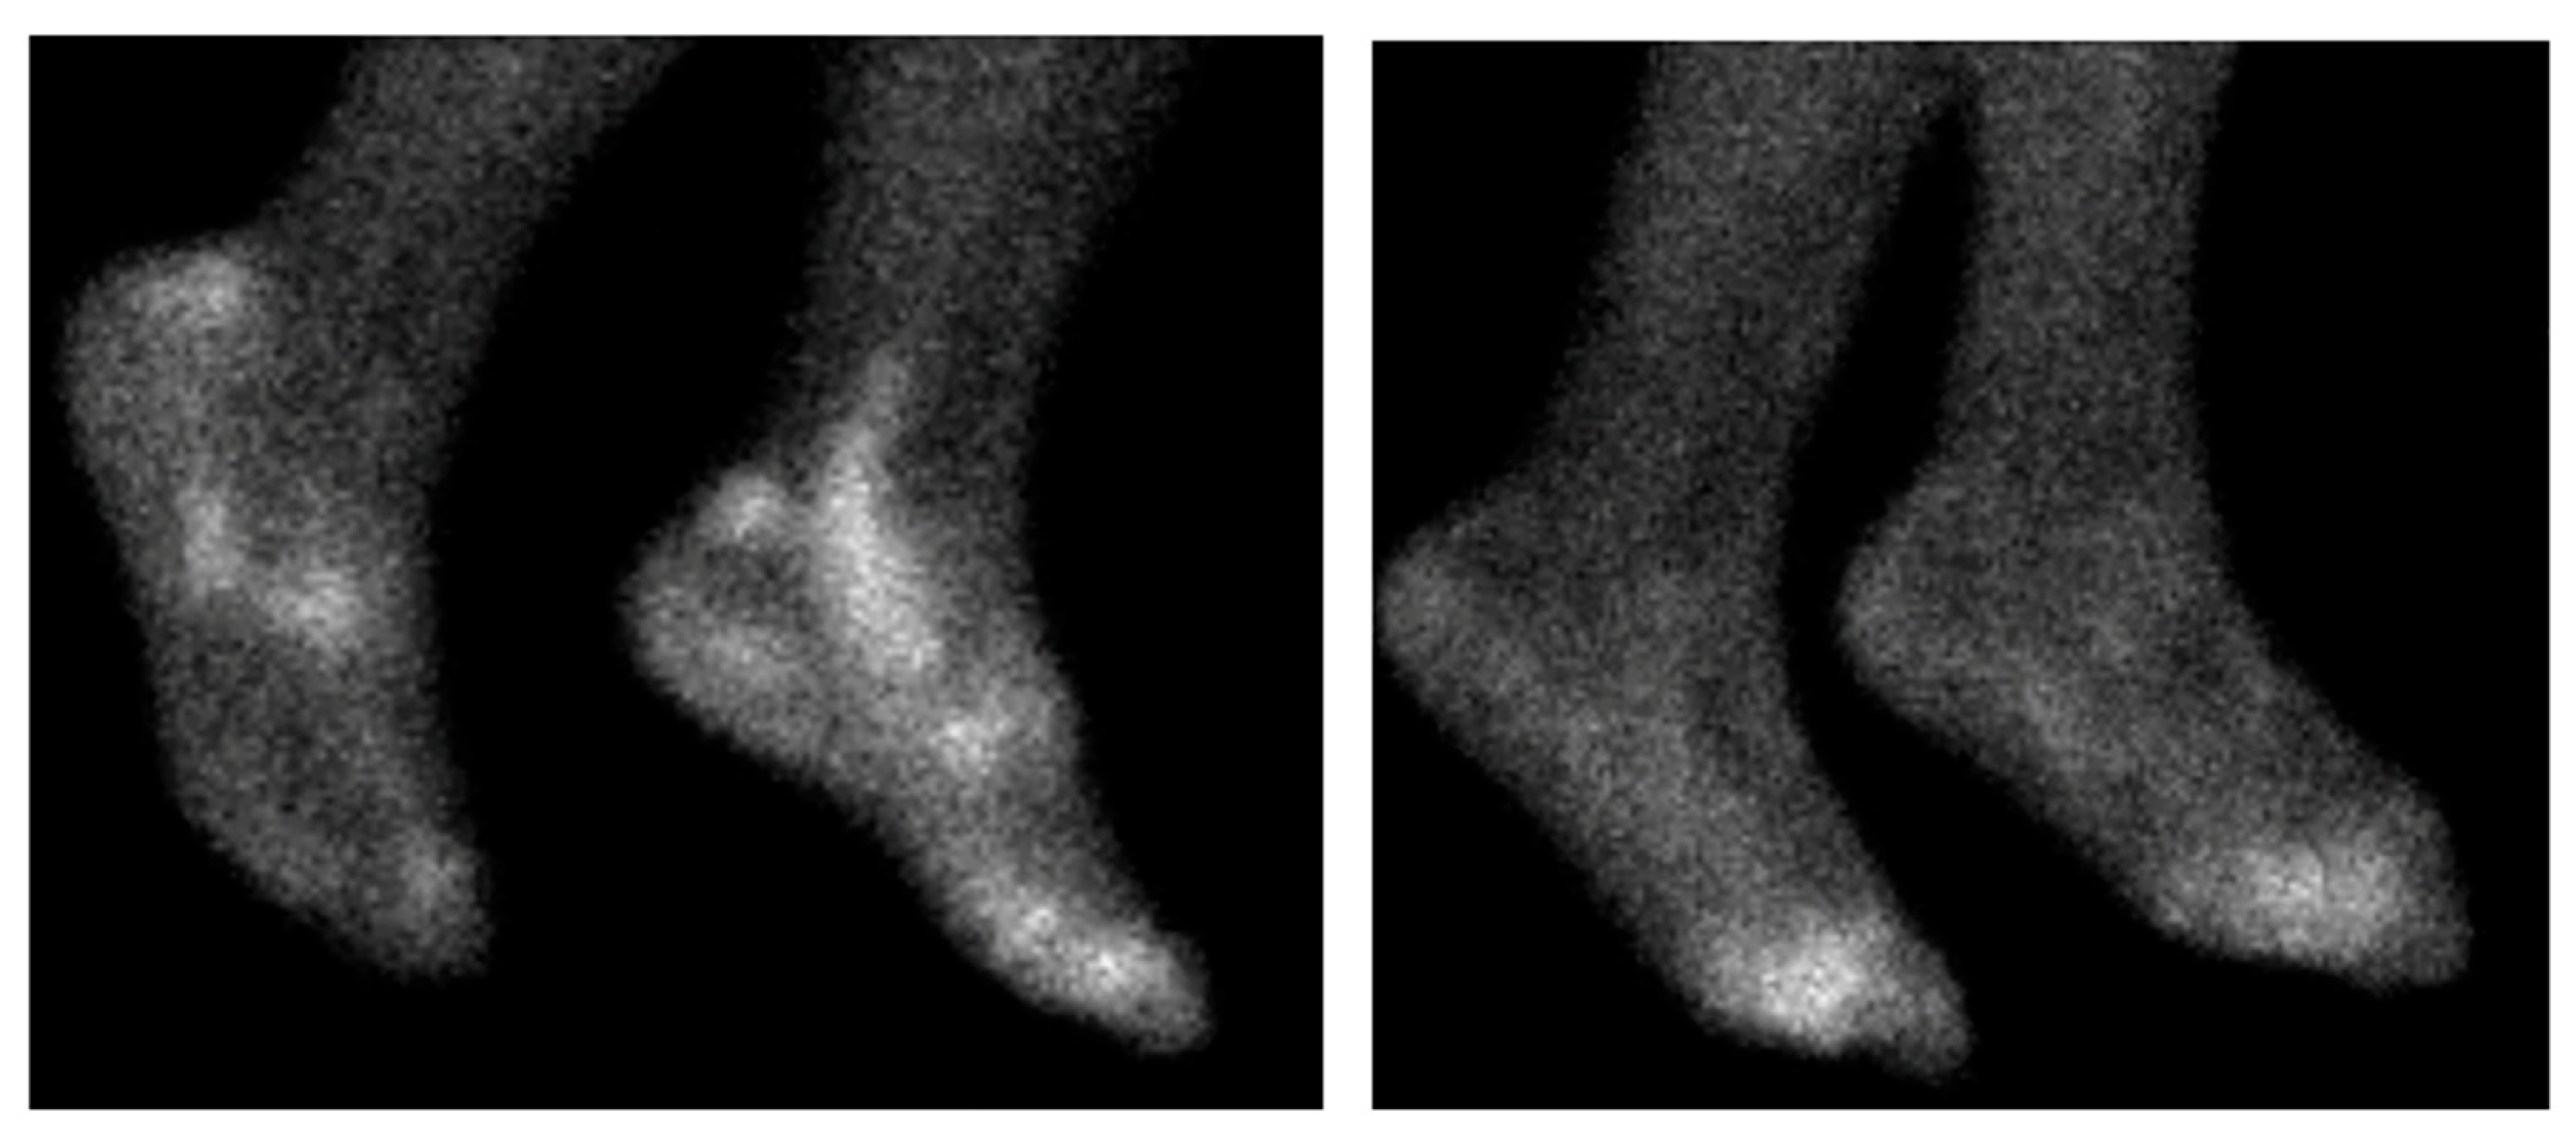

- Lee, S.J.; Hong, C.M.; Cho, I.; Ahn, B.-C.; Eun, J.S.; Kim, N.R.; Kang, J.W.; Kang, Y.M. Reappraisal of bone scintigraphy as a new tool for the evaluation of disease activity in patients with rheumatoid arthritis. Sci. Rep. 2021, 11, 21809. [Google Scholar] [CrossRef]

- Kim, J.Y.; Choi, Y.Y.; Kim, C.W.; Sung, Y.-K.; Yoo, D.-H. Bone Scintigraphy in the Diagnosis of Rheumatoid Arthritis: Is There Additional Value of Bone Scintigraphy with Blood Pool Phase over Conventional Bone Scintigraphy? J. Korean Med. Sci. 2016, 31, 502. [Google Scholar] [CrossRef]

- Park, H.J.; Chang, S.H.; Lee, J.W.; Lee, S.M. Clinical utility of F-18 sodium fluoride PET/CT for estimating disease activity in patients with rheumatoid arthritis. Quant. Imaging Med. Surg. 2021, 11, 1156–1169. [Google Scholar] [CrossRef]